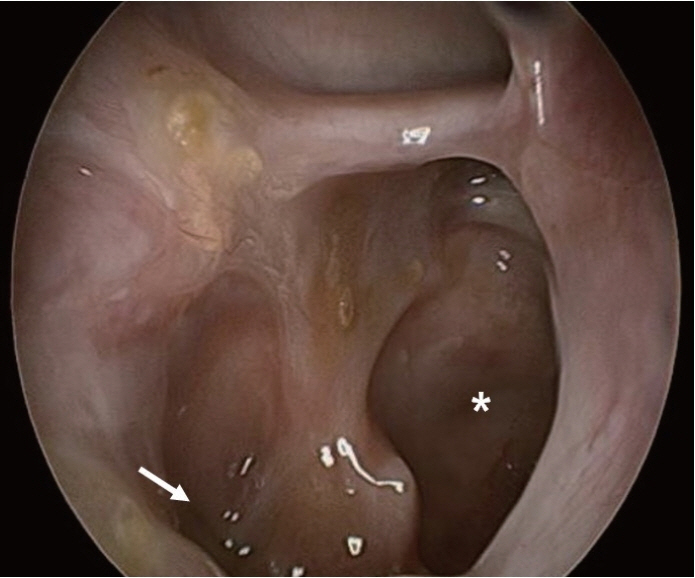

- Central skull base osteomyelitis (CSBO) is a rare, fatal condition seen mostly in elderly diabetic or immunocompromised patients; it mainly involves the sphenoid or occipital bones and diagnosis is often delayed. A 72-year-old male with diabetes was referred to our department with severe pain in the maxillary gingiva. Endoscopic biopsy of the pterygoid bone confirmed the presence of mucormycosis combined with Klebsiella pneumoniae infection. Sinus surgery was performed with bilateral alveolar bone sequestrectomy. Long-term intravenous broad-spectrum antibiotic therapy using meropenem and ampicillin/sulbactam and antifungal therapy using amphotericin B (100 mg/day) was administered; an oral antifungal agent, posaconazole (800 mg/day), was also prescribed for 11 weeks. At the 6-month follow-up visit, there were no complications and no progression of the CSBO lesion was observed. Timely diagnosis and multidisciplinary treatment including endoscopic surgery, alveolar bone sequestrectomy, and combined antifungal and antibiotic therapy can reduce mortality and minimize complications associated with CSBO.

Figure